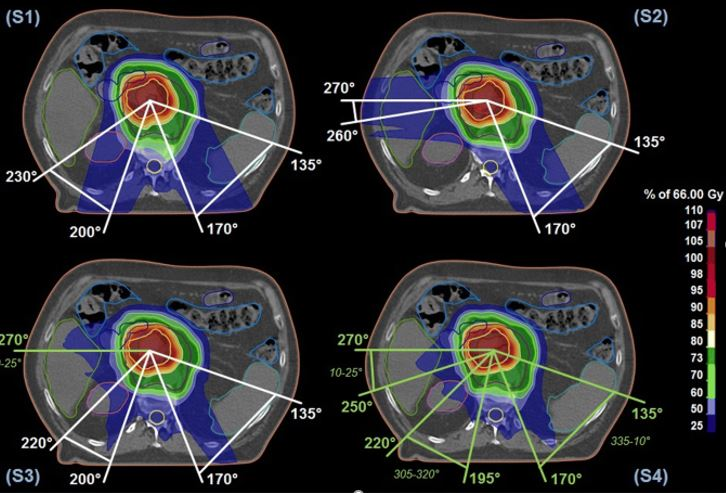

Which plan protects the OAR/small bowel the best

C